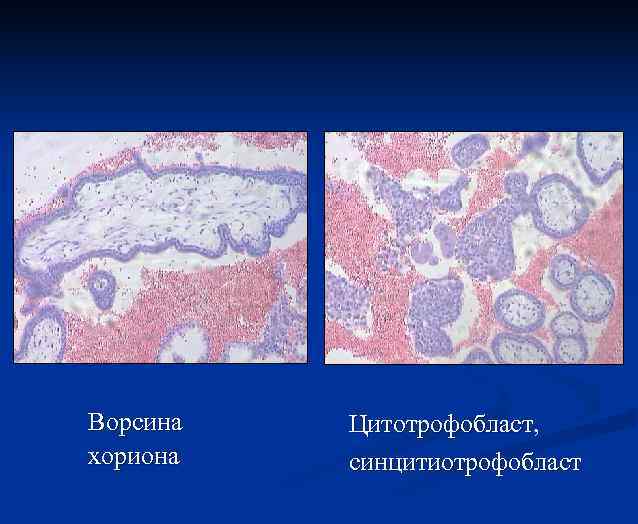

Ворсина хориона Цитотрофобласт, синцитиотрофобласт